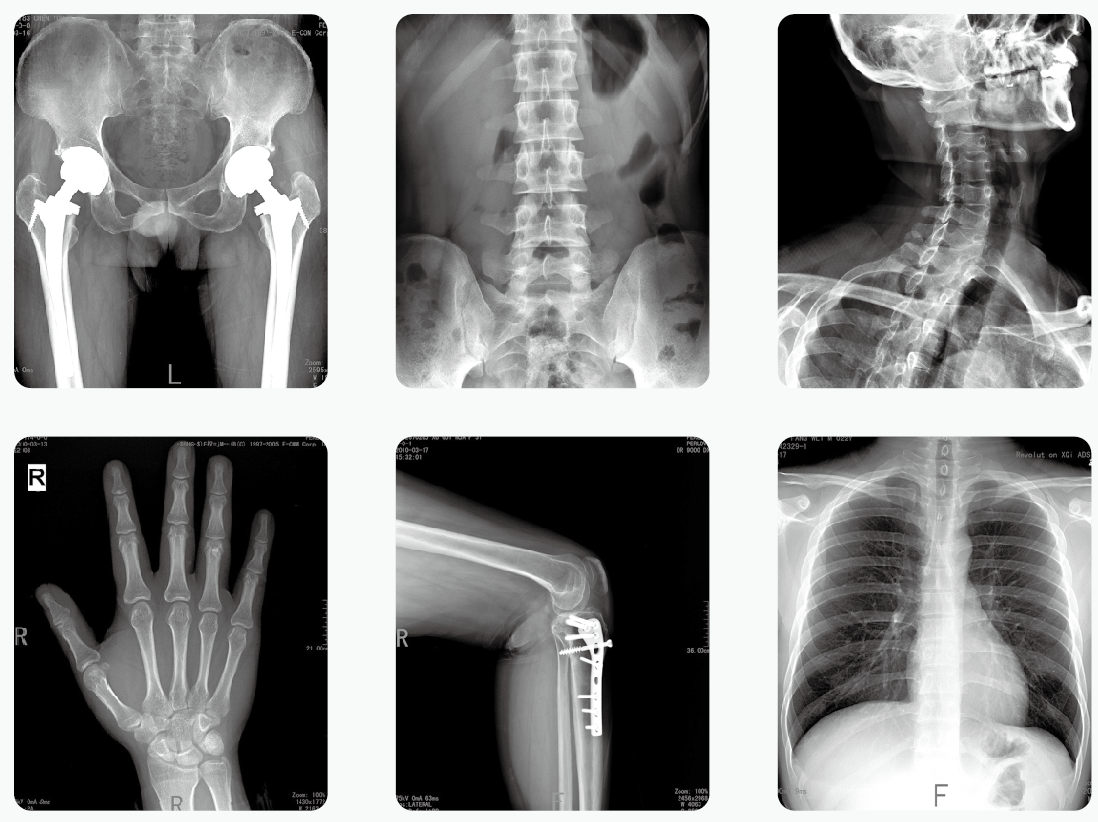

放射檢查

大家在單位例行體檢時一般會拍X光胸片,它的輻射量大約是0.1mSv;而做一次低劑量CT胸片是1mSv

1、當患者的表面癥狀不足以確診疾病,或者需進一步確定疾病的程度時,醫生確實需要借助X光機和CT等來明確診斷,才會開出檢查單。而且每一項檢查都有嚴格的適應癥,會讓患者做對應的檢查。

2、盡量選擇輻射小的檢查項目:能用低劑量技術的就不用高劑量技術;能用X線解決的就不用CT;每年必要的體檢盡量不做常規CT,而做低劑量CT篩查。

3、做放射性檢查時規范操作,對非檢查部位、重要部位采取嚴格的防護措施。如做胸部X線檢查,腹部、甲狀腺等部位會用鉛衣等防護設備予以保護。